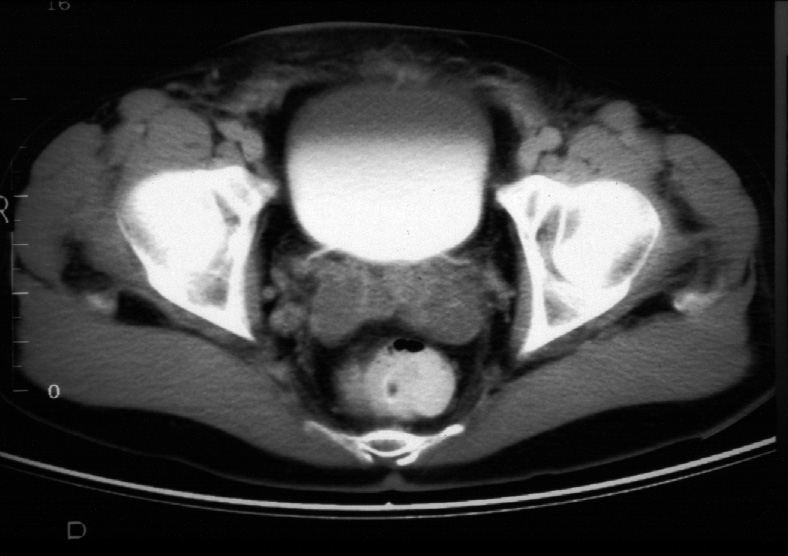

Radiology of Abdomen, Pelvis, and Perineum -- Normal Male CT of the Pelvis

Identify -- bladder, rectum, seminal visicles, femoral head